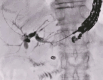

Endoscopic ultrasound-guided hepaticogastrostomy using a 22G needle with a 0.018-inch ultra-stiff guidewire without tract dilation